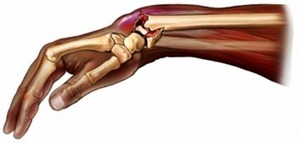

Данная травма является наиболее часто встречающейся. Это связано с тем, как располагаются конечности во время падения. Когда человек теряет равновесие, он инстинктивно пытается упасть на ладони. В результате срабатывает защитный рефлекс, позволяющий немного смягчить удар. Врачи классифицируют перелом Коллеса как разгибательный:

- При резком переносе веса тела на лучезапястный сустав, он значительно отклоняется назад.

- В такой ситуации человек стремится вернуть конечность в исходное положение, что приводит к быстрому сокращению мышц-сгибателей предплечья.

- Мягкие ткани, обладающие высокой эластичностью, легко справляются с возникающим давлением. Однако под нагрузкой они могут испытывать небольшие разрывы и растяжения.

- К сожалению, костная ткань не обладает такой же прочностью на разрыв, и это может привести к серьезным последствиям. Она должна одновременно противостоять силе тяжести тела и нагрузкам со стороны мышц и связок, которые тянут её к себе.

- Если костная ткань не выдерживает такого давления, то происходит перелом прямо над запястьем, при этом угол между отломками оказывается направленным назад.